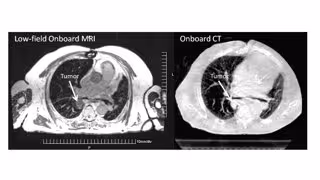

En comparación con la radioterapia estereotáctica corporal (SBRT) convencional, la tecnología MRIdian MR Linac de Genesis Care, un equipo de radioterapia adaptativa guiada por imágenes de resonancia magnética que logra tratar tumores de difícil acceso, en menos sesiones y con mínimos daños a los órganos circundantes, ha demostrado reducir la toxicidad en hasta un 76 por ciento para tumores pulmonares ultra centrales, lo que significa un gran porcentaje de disminución en los efectos secundarios producidos en el paciente durante el tratamiento.

"Gracias a los nuevos avances en radioterapia adaptativa guiada por resonancia magnética, se pueden tratar tumores de pulmón de difícil localización que de otra manera no podrían ser tratados, con excelentes resultados de eficacia y calidad de vida", apunta el oncólogo radioterápico y director médico de GenesisCare España, Felipe Couñago.